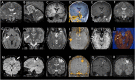

Magnetic resonance-guided laser interstitial thermal therapy (MR-gLiTT) is a novel minimally invasive treatment approach for drug-resistant focal epilepsy and brain tumors. Using thermal ablation induced by a laser diode implanted intracranially in a stereotactic manner, the technique is highly effective and safe, reducing the risk associated with more traditional open surgical approaches that could lead to increased neurological morbidity. Indications for MR-gLiTT in pediatric epilepsy surgery include hypothalamic hamartoma, tuberous sclerosis complex, cavernoma-related epilepsy, SEEG-guided seizure onset zone ablation, corpus callosotomy, periventricular nodular heterotopia, mesial temporal lobe epilepsy, and insular epilepsy. We review the available literature on the topic and present our series of patients with drug-resistant epilepsy treated by MR-gLiTT. Our experience, represented by six cases of hypothalamic hamartomas, one case of tuberous sclerosis, and one case of dysembryoplastic neuroepithelial tumor, helps to confirm that MR-gLiTT is a highly safe and effective procedure for several epilepsy conditions in children.